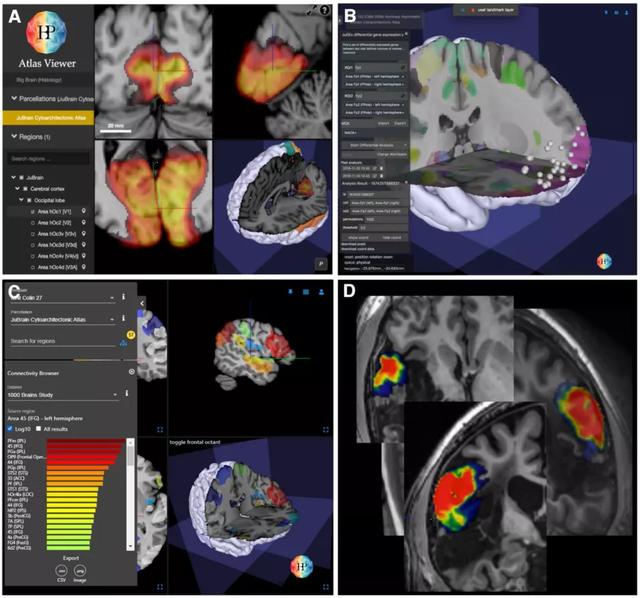

Julich 脑图谱是用一个模块化的、灵活的、自适应的框架来创建概率性的细胞结构图谱。在一个共同的立体定位参考空间中,Julich脑图谱允许比较不同研究中获得的功能激活、网络、基因表达模式、解剖结构和其他数据(图3)。

图3:Julich脑图谱应用举例。(A)人脑HBP图谱中显示是基于网络图谱工具的的概率图。(B) JuGEx能够分析细胞结构图(C) 中的差异基因表达,探索基于DTI的连通性(如左Broca's 45区)。(D)在一名脑损伤和失语症患者的数据集上叠加Broca 44区的概率图。该图谱可以精确地描述神经影像学发现的微观解剖位置,并且使用图谱作为一个掩模工具来量化这些发现。